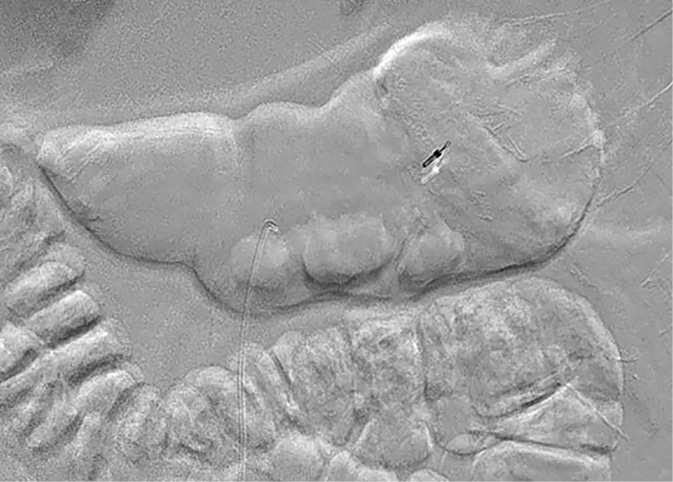

A 55-year-old male patient arrived at the Emergency Department of the Republican Vilnius University Hospital complaining of black stools and general weakness for only 1-day, tachycardia and low arterial blood pressure. UGIB was suspected. An extra esophagogastroduodenoscopy was performed. Arterial bleeding was observed from the posterior stomach wall in the border of the body/upper third of the stomach (Figures 1, 2). No pathological formations were visible in the mucosa. Dieulafoy’s lesion was suspected. The abdominal surgeon/endoscopist immediately started to stop the bleeding with adrenaline injection, but it was not enough. When we used endoscopic clip (Figures 3, 4). Bleeding was completely stopped. Patient’s condition was stabilized. But disease remained unknown. In order to reduce the risk of recurrent bleeding, we performed selective angiography of truncus coeliacus and embolization of the distal branches of arteria gastrica sinistra and some arteria lienalis branches, that feed formation through collateral blood flow (Figure 5). Large microspheres and pushing spirals were used for embolization (Figures 6, 7). The cause of bleeding still remained surely unknown. Now we suspected tumor. Only after by detailed strict anamnesis based on the patient’s life history, we conclude that the patient has a genetic disorder – Grönblad-Strandberg syndrome. According to our data, only four people suffer from this syndrome in Lithuania. Adjacent to this the patient had been operated for rectal cancer in the past, followed by ileostomy closure and abdominal wall hernioplasty for postoperative hernia. It is currently known that the patient has metastases in the liver and brain. The spread of cancer metastases, wide and severe comorbidities worsen the patient’s current condition, but despise these severe illnesses after proper and timely interventions, the patient lives without recurrent bleeding until now.

Figure 4. Clip (angiographic view)